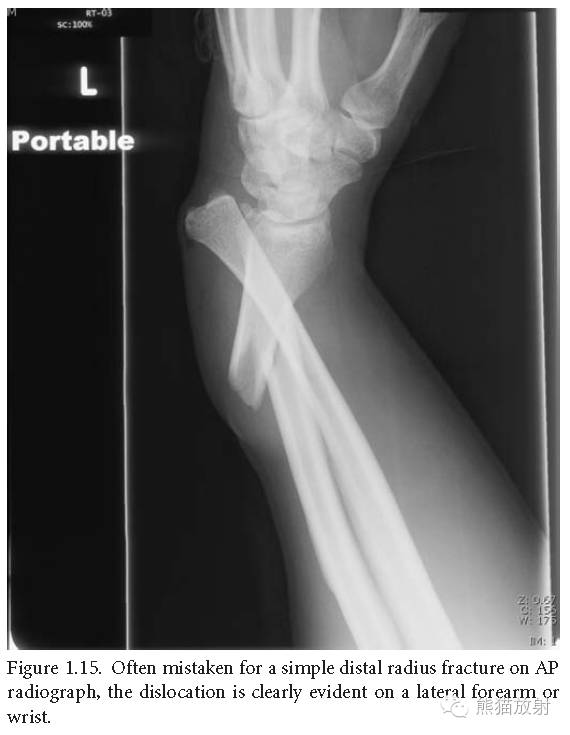

盖氏骨折:桡骨中下1/3骨折合并下尺桡关节脱位;与孟氏骨折完全相反,也是由前臂旋转暴力所致,但较孟氏骨折更为常见。

盖氏骨折:在正位片上常被误认为简单的桡骨远段骨折,在侧位片上脱位显示的更加明显。